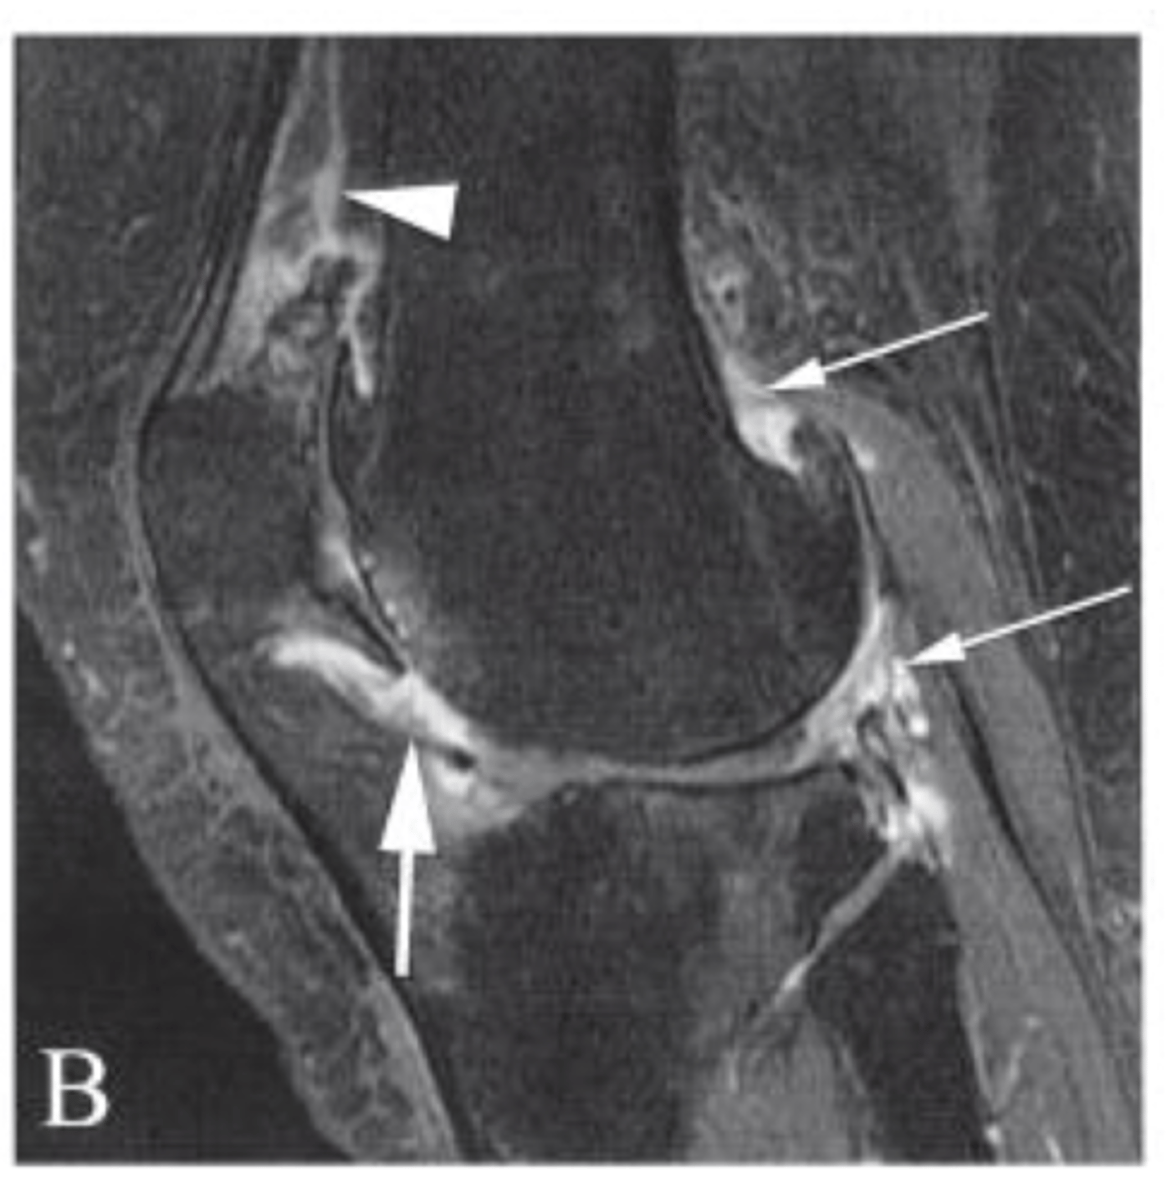

Bone edema/bone bruise

Define the pathology.

Label 1-9.

ACL (always goes inferior --> superior in a posterior direction)

Which ligament can you see in this sagittal view?